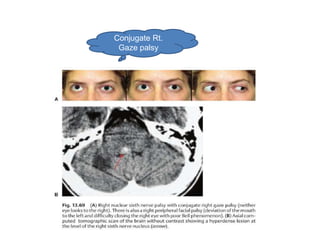

Conjugate Rt.

Gaze palsy

Horizontal gaze paresis

• Lesion of 6th n. nucleus

– Loss of ipsilat. Voluntary and reflexive conjugate

movement

– Ipsilat. Facial weakness

Horizontal gaze paresis •Lesion of 6th n. nucleus – Loss of ipsilat. Voluntary and reflexive conjugate movement – Ipsilat. Facial weakness